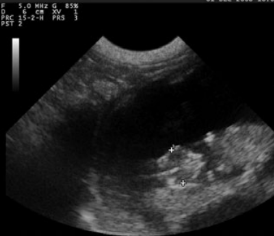

羊用B超机对双顶径(BPD)的测定

BPD的超声测量是常规的在产前检查和估计期间进行各种山羊品种中的GA含量,测量的标准BPD如下:尽可能椭圆形,封闭头骨表轮廓,大脑中线分裂克将半球分成两个等距的部分并测量-取自近端的外表面颅骨到远端颅骨内表面。头部扫描应在轴向平面上进行。图像对称性对于准确测量至关重要。很高相关性之间妊娠中期GA和BPD已经升高,BPD是也很难之后测量胎儿出生后第95天胎儿其他部位压迫头部,和也的变化性的胎儿的位置和姿势。因此,据报道,相关系数较低第60至135天之间的韩国黑山羊妊娠。

图3超声检查图片的双顶直径上胎儿在妊娠40天